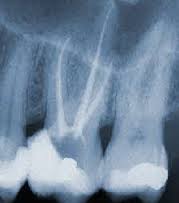

Лечение корневого канала - это лечение внутренних областей зуба, а именно той зоны, которую занимает пульпа - нервная ткань зуба. Это процедура состоит в удалении пораженного нерва и обработке прилегающих тканей. Последний этап – это заполнение и пломбирование пространства зубного нерва таким образом, что бактериям не остается места для существования.